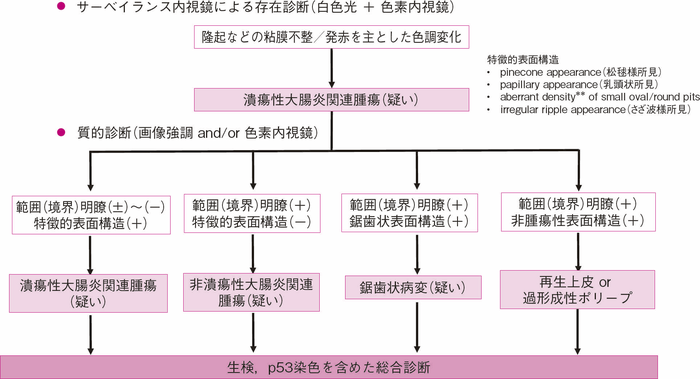

図4 UC関連大腸腫瘍 診断アルゴリズム

拡大内視鏡検査を用いたpit pattern診断に関する検討が国内外から報告されており7,12,13),厚生労働省研究班の合同班会議でUC関連大腸腫瘍におけるpit pattern分類としてのNPUC分類14)が提唱されたが,広い普及までには至らなかった。病変周囲の非腫瘍性再生上皮と腺腫性pit patternが酷似していることも多く,従来の上皮性腫瘍に用いられている工藤・鶴田分類をUC関連大腸腫瘍に対する腫瘍・非腫瘍の鑑別にそのまま当てはめることには限界があると考えられる7,15)。また,異型度の診断においても同様で,癌であった場合の深達度診断は,特異度は極めて高いものの,感度は低いとされている。しかし,pit patternのみならず,その領域性を加味することでUC関連大腸腫瘍の診断の絞り込みが可能であると考えられている(図4)。さらには,内視鏡検査所見に加えて,臨床情報や生検による病理組織学的(Ki-67やp53の免疫染色を含む)所見も加えて総合的に診断することが現時点では推奨される。